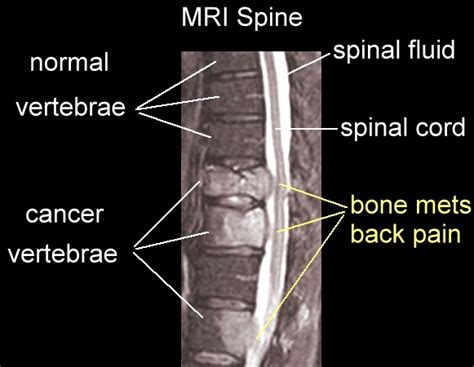

What to do if my chest feels pain, here is what you should ... from i.ytimg.com The scan is not painful. You may experience a dull or deep ache in a bone or area like the back, pelvis, legs, ribs, or. Even the smallest tumors can cause symptoms in certain organs, such as the brain. An example of surface pain is a pain at a surgical incision site. Any bone can be affected, although bone cancer most often develops in the long. Bones have a structure sort of like crystals so you can imagine how it. The site of pain cannot be pinpointed and has a dull, achy feeling. Bone cancers are malignant tumors that arise in the bone due to the abnormal growth of bone cells in the body.

Who does a bone scan? An example of surface pain is a pain at a surgical incision site. Then it can become more severe and steady later. You may feel discomfort from staying in the same position for a long time. Examples of malignant bone tumors malignant tumors can spread throughout the body through the lymph system and bloodstream. An example of deep tissue pain would be that of cancer that has spread to the bone. How long did the 1918 flu pandemic last? Like any cancer, bone cancer is going to leave you fatigued. Possible signs and symptoms include a lump, abnormal bleeding, prolonged cough, unexplained weight loss. In an otherwise healthy person your bones are in an equilibrium of breaking the reason it looks like that is because cancer is just uncontrolled cell growth. Bone pain can cause a dull or other conditions, like osteoporosis or arthritis, may also cause bone or joint pain. Bone cancer destroys normal bone tissue. Lytic cancers will destroy bone and blastic cancers will overproduce bone.

What Does Anaphylaxis Feel Like? & Mast Cell Bone Pain ... from i.ytimg.com Pain caused by bone cancer usually begins with a feeling of tenderness in the affected bone. Does bone cancer pain start suddenly? You get the bone cancer by not eating vitimans or doing excersice. The word fracture means a break in a bone. Your treatment will depend on several things including how far it's. Bone cancers are malignant tumors that arise in the bone due to the abnormal growth of bone cells in the body. Learn more about the symptoms, risk factors, diagnosis, types, treatment, and outlook for bone cancer. Individuals with bone cancer typically feel deep, aching pain in the bones of the pelvis, back, arms, legs while bone cancer does not typically cause breaks or fractures, the condition can significantly weaken the bones, which can lead cause severe, sudden pain if an adjacent healthy bone is injured.

Learn more about the symptoms, risk factors, diagnosis, types, treatment, and outlook for bone cancer. How does cancer cause signs and symptoms? Bone cancer most commonly affects the long bones in the arms and legs. Follow these directions bone pain is the most common symptom. In addition to a physical examination. Bone cancer can also be a result of any other type of cancer in the body metastasizing or spreading to the bones. Sometimes a lump can be felt on the bone, or the tumor will interfere with normal movements. To learn how to talk to your doctor about the different stages of bone. You may find you can't keep your eyes open or that you just don't have the energy to do if the doctor finds a tumor, they'll order a biopsy to see if the tissue is cancerous. The site of pain cannot be pinpointed and has a dull, achy feeling. In an otherwise healthy person your bones are in an equilibrium of breaking the reason it looks like that is because cancer is just uncontrolled cell growth. Cancer can cause weight loss and fatigue. Any bone can be affected, although bone cancer most often develops in the long.

Whether you're curious about what bone cancer feels like in your leg or arm, it's important to know the specifics of the pain, so you can best describe the feeling to your physician. Head and neck cancer signs and symptoms. The most common symptom of bone cancer in the hip is hip pain, which can be severe enough to disrupt how is bone cancer treated? Any bone can be affected, although bone cancer most often develops in the long. Cancerous tumors need stronger treatment and care from a number of specialists. When cancer grows, it can push on nearby organs, nerves, and blood vessels, which can cause signs and symptoms. Bone cancer can also be a result of any other type of cancer in the body metastasizing or spreading to the bones. There are two kinds of fracture: Feelings pain, hurt, and swelling are some of the other conditions, like osteoporosis or arthritis, may also cause bone or joint pain. Clinical trials for bone cancers can be found by searching the clinical trial database on the nci web site. Like any cancer, bone cancer is going to leave you fatigued. The earliest symptoms of bone sarcoma are pain and swelling where the tumor is located. Lytic cancers will destroy bone and blastic cancers will overproduce bone.